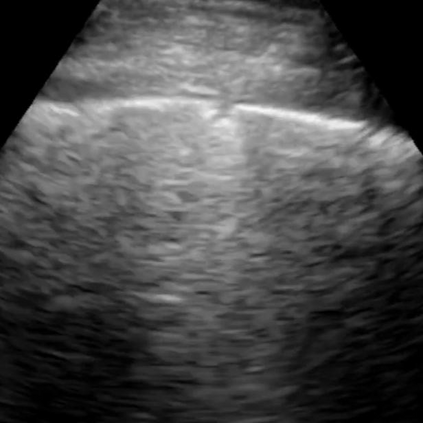

Most deep neural networks (DNNs) based ultrasound (US) medical image analysis models use pretrained backbones (e.g., ImageNet) for better model generalization. However, the domain gap between natural and medical images causes an inevitable performance bottleneck. To alleviate this problem, an US dataset named US-4 is constructed for direct pretraining on the same domain. It contains over 23,000 images from four US video sub-datasets. To learn robust features from US-4, we propose an US semi-supervised contrastive learning method, named USCL, for pretraining. In order to avoid high similarities between negative pairs as well as mine abundant visual features from limited US videos, USCL adopts a sample pair generation method to enrich the feature involved in a single step of contrastive optimization. Extensive experiments on several downstream tasks show the superiority of USCL pretraining against ImageNet pretraining and other state-of-the-art (SOTA) pretraining approaches. In particular, USCL pretrained backbone achieves fine-tuning accuracy of over 94% on POCUS dataset, which is 10% higher than 84% of the ImageNet pretrained model. The source codes of this work are available at https://github.com/983632847/USCL.